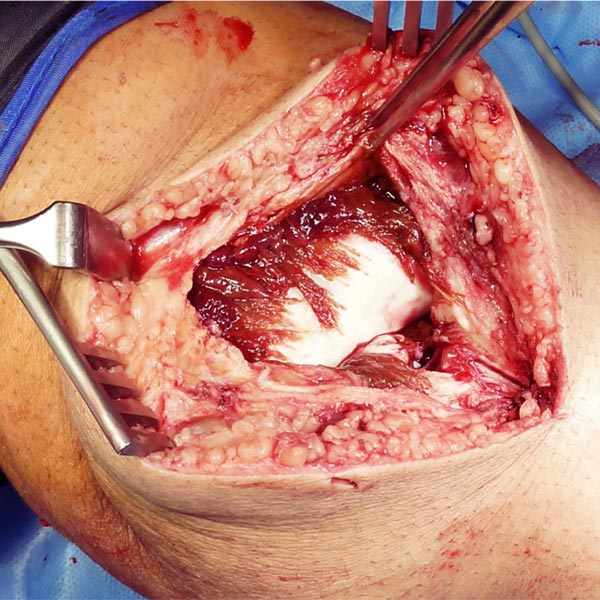

Intraoperatives Bild nach Entfernung der Synovia sowie der intraartikulären venösen Malformation. Noch vorhandene Reste der venösen Malformation über dem vorderen Kreuzband. Ausgedehnter, flächiger Knorpelschaden am lateralen Femurkondylus.

Die venöse Malformation wurde ganz entfernt, das vordere Kreuzband ist jetzt wieder voll sichtbar. Der Knorpelschaden wurde durch eine sog. Extrazelluläre Matrix gedeckt und behandelt.